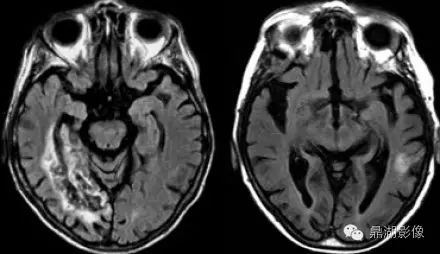

大脑中动脉梗塞(同时累及深穿支及皮层支)

a345d755a0bb4289fe7ce0f3edc883ef.jpg